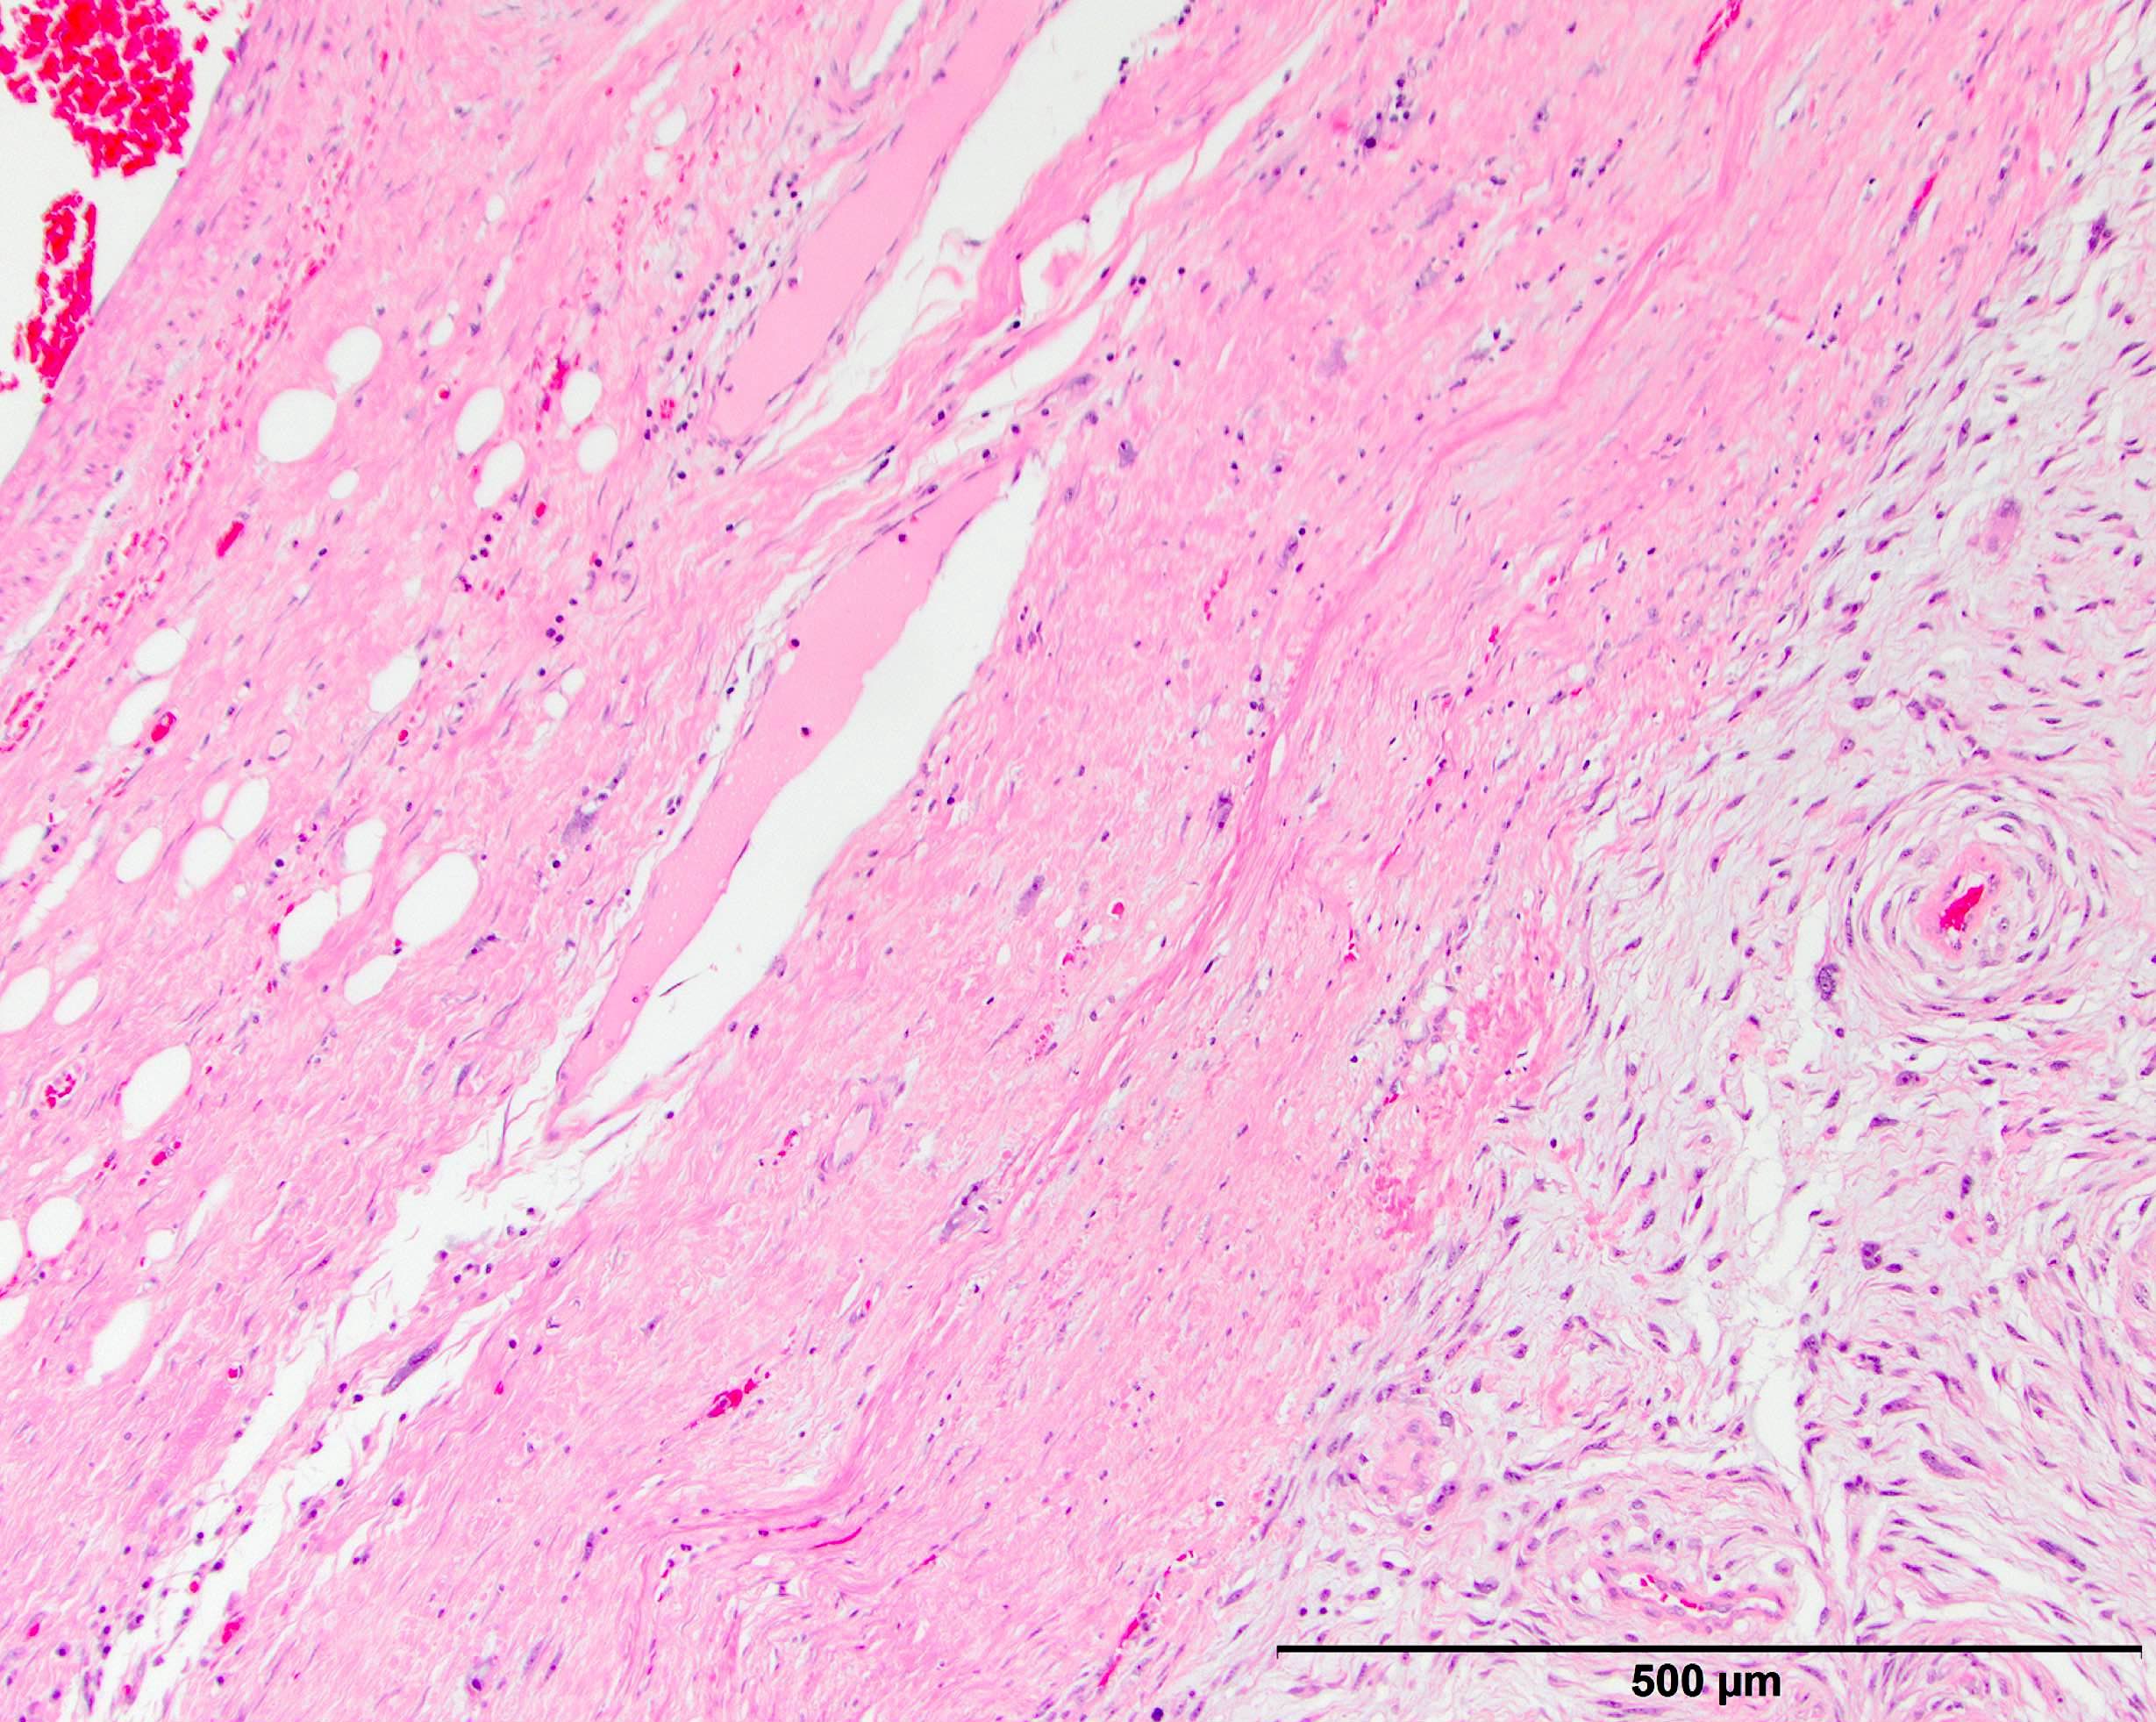

Microscopic (histologic) description

- High grade dedifferentiated liposarcoma

- Well differentiated and dedifferentiated components are often both present and can have abrupt or gradual transitions

- Dedifferentiated component is a cellular and typically a nonlipogenic sarcoma with significant pleomorphism

- Although some propose a mitotic rate of > 5 mitoses/10 high power fields, this is not uniformly adopted (Am J Surg Pathol 2023;47:649)

- Often resembles malignant fibrous histiocytoma (MFH), now referred to as undifferentiated pleomorphic sarcoma (UPS), with short fascicles of pleomorphic spindle cells associated with mixed inflammatory infiltrate

- Can show a peculiar whirling pattern reminiscent of meningothelial structures (Histopathology 1998;33:414, Am J Surg Pathol 1998;22:945)

- Heterologous elements in 5 - 10% of cases

- Heterologous elements can easily mislead pathologists in poorly sampled cases, especially in metastatic sites

- Can manifest as neural differentiation, leiomyosarcoma, osteosarcoma / chondrosarcoma, rhabdomyosarcoma or pleomorphic liposarcoma (homologous lipoblastic dedifferentiation)

- Rhabdomyoblastic differentiation has been associated with worse outcomes

- Angiosarcomatous differentiation has been reported (Virchows Arch 2005;446:456)

- Myxoid liposarcoma-like morphologic features may exist in a subset of cases (often with coexisting amplification of DDIT3) and are important to recognize as a unique histologic pattern of dedifferentiated liposarcoma to avoid misclassification as myxoid liposarcoma (Mod Pathol 2019;32:585)

- Low grade dedifferentiated liposarcoma

- Less common low grade tumor resembling fibromatosis or well differentiated fibrosarcoma

- Nonlipogenic (in contrast to well differentiated spindle cell liposarcoma, which contains atypical fat / lipoblasts)

- Considered by some to be the same as cellular atypical lipomatous tumor, although there is evidence that even low grade dedifferentiation is associated with a poorer prognosis when compared with conventional atypical lipomatous tumor

- Now a recognized WHO classification

- Pitfalls and tips

- Look at the edges of dedifferentiated liposarcoma to identify a rim of background well differentiated liposarcoma that may mimic compressed background fat with reactive change

- Dedifferentiated liposarcoma often shows a significant amount of heterogeneity (multiple patterns of differentiation and growth) and the confusing nature of the tumor can be a clue to the correct diagnosis

- Imaging may show both a fatty and solid nonfatty component

- Metastases often contain only the dedifferentiated component

- When in doubt use ancillary testing to confirm either protein overexpression or gene amplification

Microscopic (histologic) images

Contributed by Michael R. Clay, M.D. and AFIP